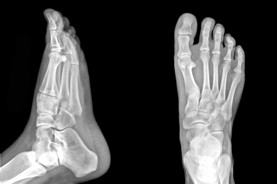

PAINFUL OR UNSIGHTLY BUNIONS?

At the Red Deer Foot Institute, our Doctors are trained to specifically treat problems associated with your feet or ankles. Below are several of the most common problems that we see on a day to day basis: